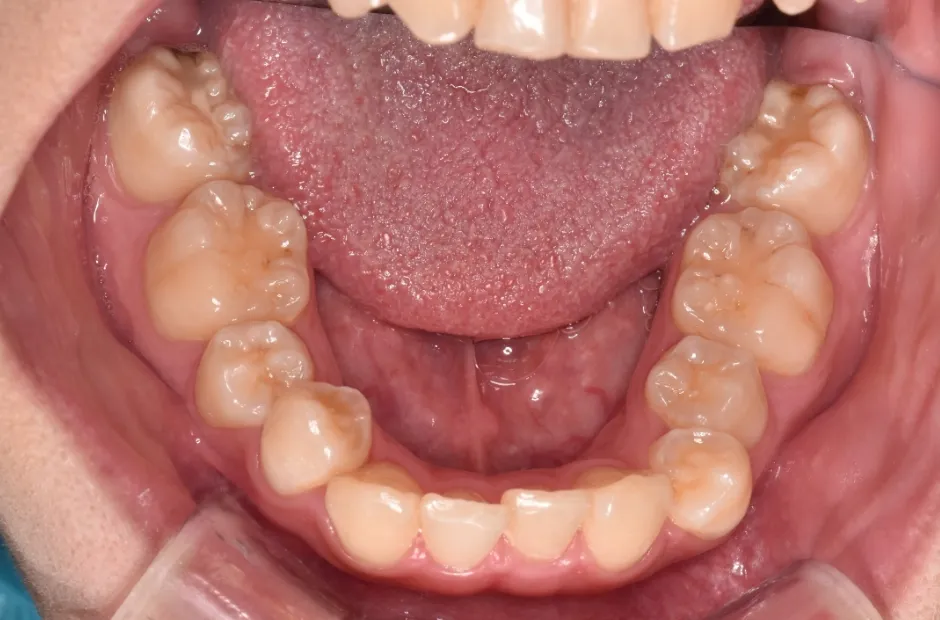

開咬

| 診断名・主訴 | 開咬 |

|---|---|

| 年齢・性別 | 18歳・男性 |

| 治療期間・回数 | 1年 12回 |

| 治療に用いた主な装置 | ロール付きリンガルアーチ |

| 抜歯部位 | なし |

| 治療費 | 70万円(税抜) |

| リスク・副作用 | 装置による違和感・疼痛・歯肉退縮・歯根吸収・虫歯のリスクなど |

治療前

治療中

治療後